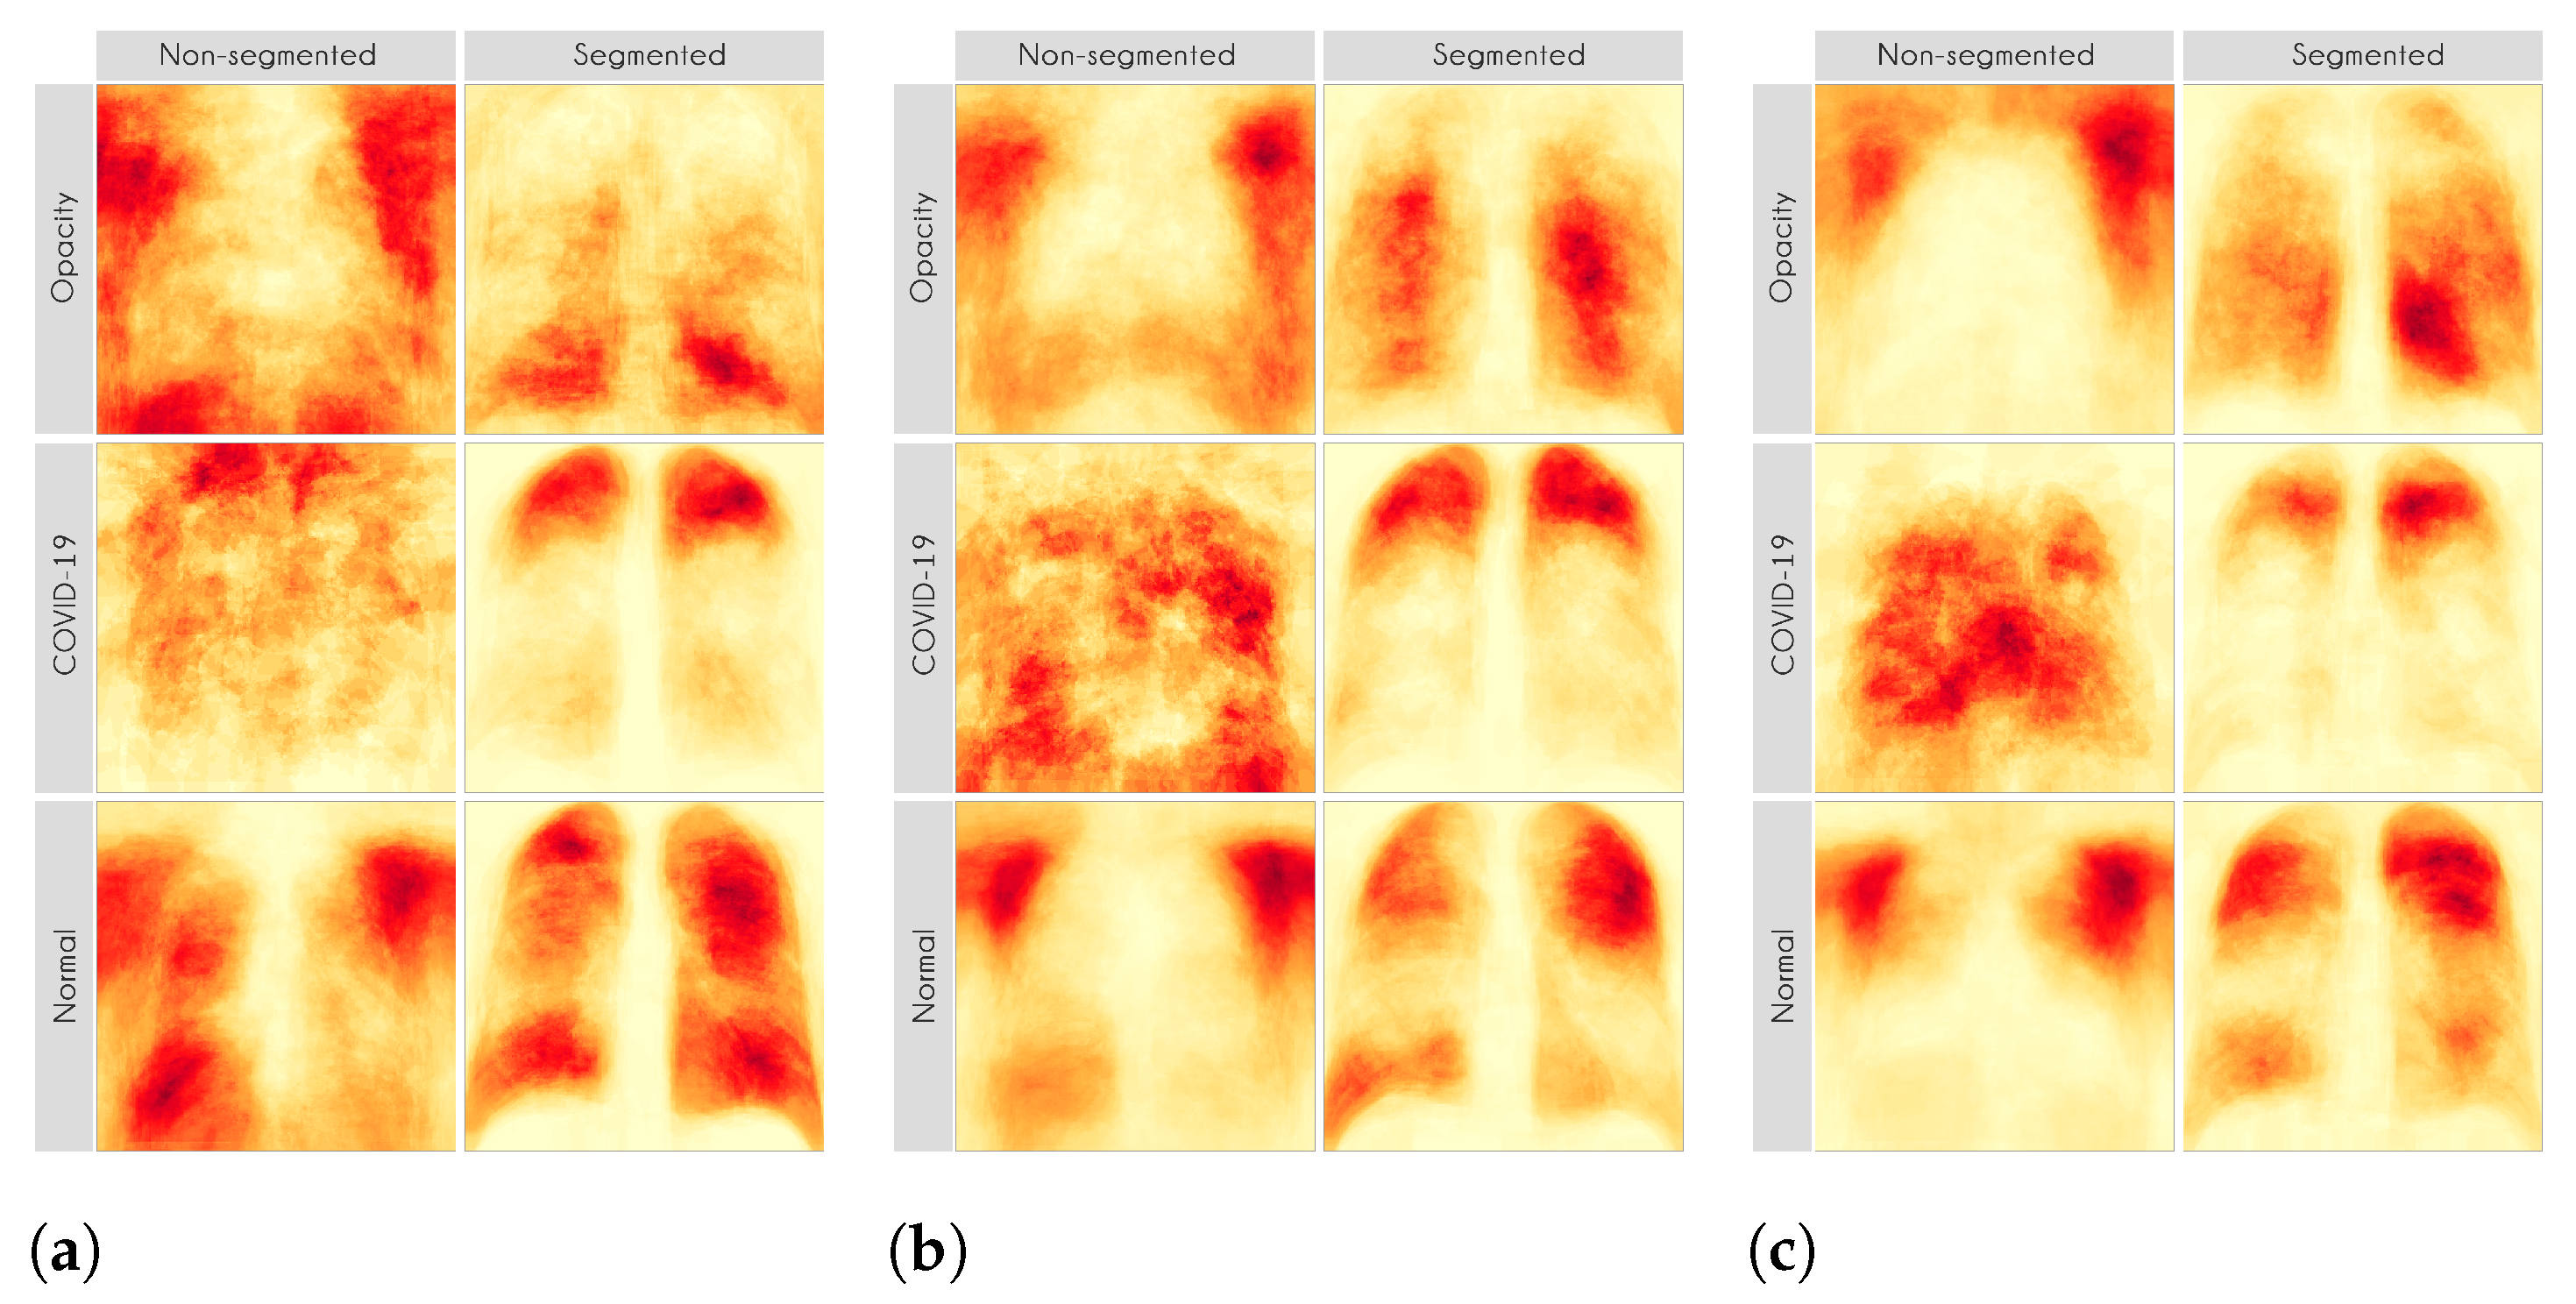

Figure 7 and

Figure 8 shows examples of important regions highlighted by LIME and Grad-CAM, respectively. In

Section 4, we will show that models trained using segmented lungs focus primarily on the lung area, while models trained using full CXR images frequently focus elsewhere.

Figure 13 presents some examples of the Grad-CAM explanation showing that the model is actively using burned-in annotations for the prediction. The LIME heatmaps presented in

Figure 10 show that exactly behavior for the classes Lung opacity and Normal in the non-segmented models, i.e., the model learned to identify the annotations and not lung opacities. The Grad-CAM heatmaps in

Our XAI approach is novel in the sense that we explored a more general explanation instead of focusing on single examples. In the literature, there are many papers exploring LIME and Grad-CAM for a couple of handpicked examples. The main problem with such approaches is that the examples might have been eventually chosen to reach a specific result. In this paper, we applied the XAI techniques to each image in the test set individually and created a heatmap aggregating all individual results to represent a broader context, which indicates which portions of the CXR image the models have focused on for prediction.

Figure 10 and

Figure 11 demonstrate that the models using full CXR images are misleading because they focus a lot on the left and right uppermost regions, which is usually the location of burned-in annotations.